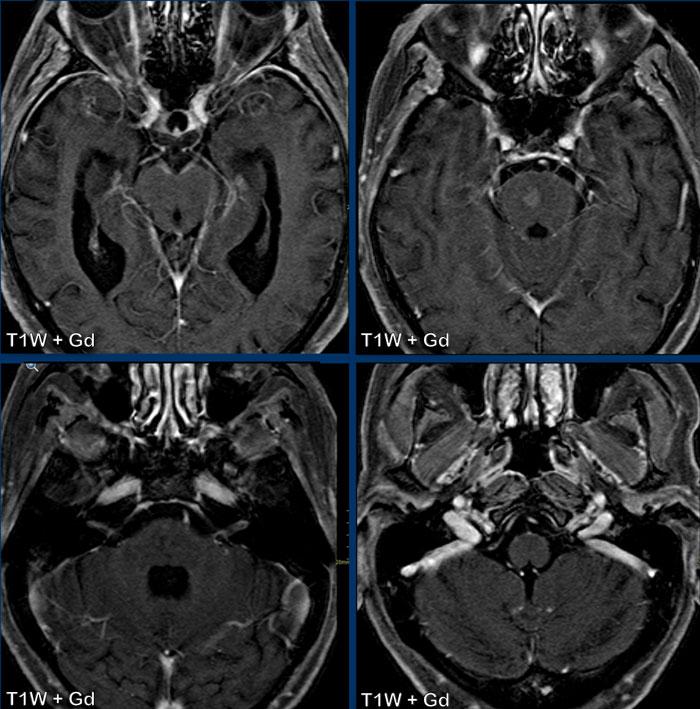

Các hình ảnh này thuộc về một bệnh nhân HIV đã bắt đầu điều trị HAART 2 tuần trước và nhập viện vì rối loạn hành vi.

Hình ảnh

Trên chuỗi xung T2W, chất trắng thùy trán phải tăng tín hiệu.

Lưu ý hình ảnh ngấm thuốc dạng chấm trên các lát cắt axial, thực chất là dạng tuyến tính trên các lát cắt coronal hoặc sagittal (không hiển thị).

Đây là kiểu ngấm thuốc quanh mạch máu và kết hợp với tiền sử bệnh, chẩn đoán là PML-IRIS.

Đây là một bệnh nhân HIV khác, đã bắt đầu điều trị HAART được hai tháng.

Số lượng CD4 ở mức tốt.

Tuy nhiên, bệnh nhân có liệt tiến triển và xuất hiện nhiều cơn động kinh hơn.

Hình ảnh cho thấy các tổn thương chất trắng hai bên lan rộng với ngấm thuốc dạng chấm trên chuỗi xung T1W sau tiêm thuốc tương phản từ.

Chẩn đoán PML-IRIS được xác lập và bệnh nhân được điều trị bằng corticosteroid.